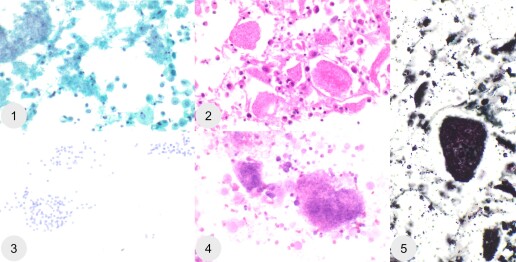

April 2026: The Many Faces of Pneumocystis jirovecii (BAL)

1. Upper left: PAP, 400x (smear)

2. Upper middle: MGG, 400x (smear)

3. Lower left: Toluidine blue, 400x (smear)

4. Lower right: HE, 400x (cell block)

5. Right: GMC, 400x (cell block)

Bild von Verónica Cabezas, Kantonsspital Graubünden